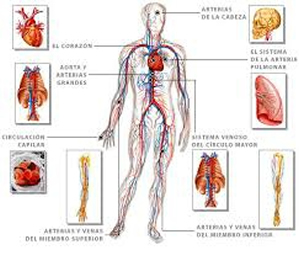

- En el sistema cardíaco, con el corazón y los vasos sanguíneos como protagonistas, que se encargan de transportar sangre con oxígeno y nutrientes hacia todas las células del organismo y de llevar los desechos de éstas hacia los pulmones

Los complejos mecanismos por los que actúan estos y otros sistemas, como el digestivo, el respiratorio y el inmunológico, permiten que un cuerpo conserve su estado de salud, gracias al trabajo en equipo ejercido por la unidad funcional básica de nuestro cuerpo: la célula.

Si bien su tamaño es pequeño, su cantidad es numerosa, son 100 millones de engranes trabajando en conjunto, para que los distintos sistemas que componen a esta máquina, lo hagan armoniosamente y cabalmente se cumpla su carácter de Perfecta.

Si esto sucede, a través de un proceso llamado “autointoxicación”, estas sustancias tóxicas pueden ser transportadas al torrente sanguíneo, donde los sistemas linfático y circulatorio, así como los pulmones y los riñones, se sobrecargan y nos exponen a graves riesgos de salud.